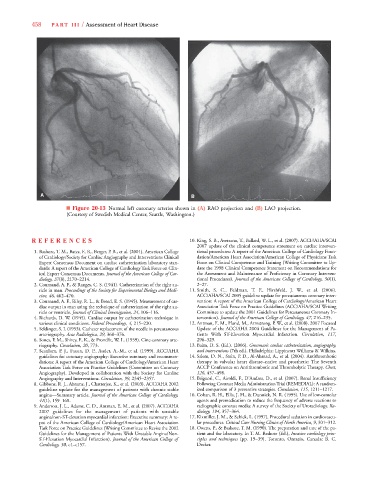

■ Figure 20-13 Normal left coronary arteries shown in (A) RAO projection and (B) LAO projection.

(Courtesy of Swedish Medical Center, Seattle, Washington.)